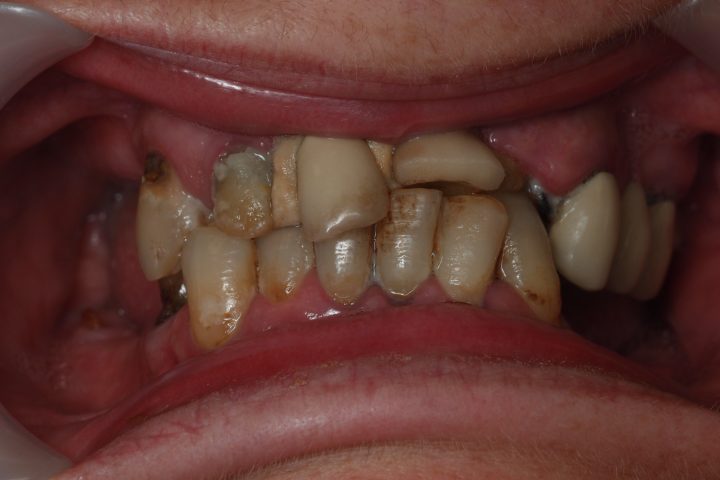

Clive kam aus England, und war im Jahr 2016 bei uns. Früher war er Berufsboxer, deswegen hatte er abgehärmte Zähne. Bis seinem 50. Geburtstag hat er sehr viele Zähne verloren, und die übrigen waren abgebrochen und verfärbt.

Er hatte 10 Tage lange Behandlung in der Zahnklinik Centrocc Dental. Sein Traum wurde erfüllt, Frau Dr. Erdélyi hat ihm schneeweißes, ausgezeichnetes Lächeln mit der Hilfe von 18 Stück Metallkeramik Kronen gezaubert.